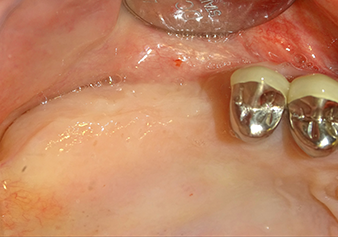

A 49-year-old female patient, a non-smoker and with nothing remarkable in her general medical history, was referred to our oral surgery practice for surgical extraction of tooth 16 and subsequent implantation. After the extraction, the patient experienced mild sinusitis trouble with the resultthat we initially waited six months before carrying out the measure. The residual bone height at the planned implant position measured 3-4 mm (Fig. 1 and 2).

Preoperative findings: The alveolar ridge has healed well, including sufficiently broad, keratinised gingiva

Fig.1: Preoperative findings: The alveolar ridge has healed well, including sufficiently broad, keratinised gingiva.